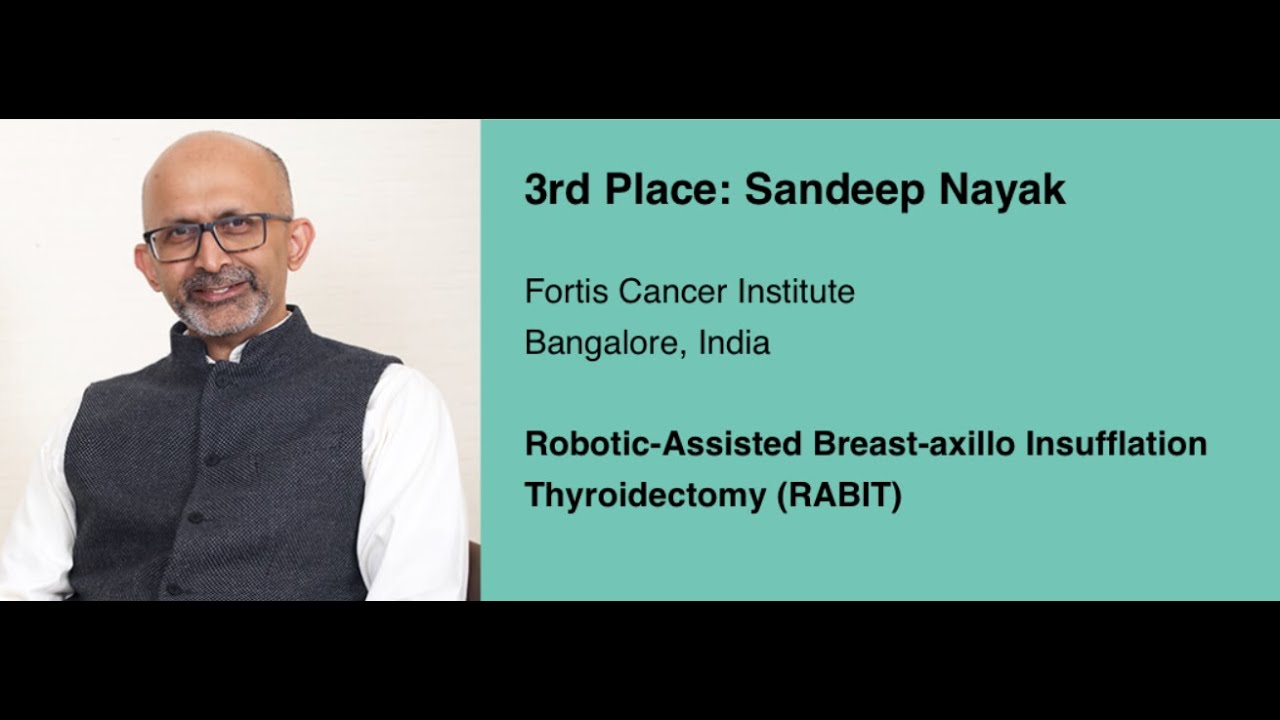

3rd Place: #217- Dr. Sandeep Nayak: Robotic-Assisted Breast-axillo Insufflation Thyroidectomy (RABIT)

KS Awards, Robotics, Surgeon ';